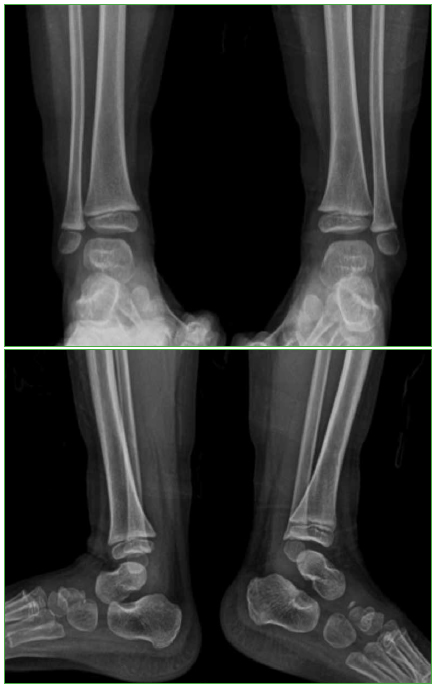

Tibia osteomyelitis secondary to BCG vaccination in an immunocompetent infant. Case report

Introduction: The Bacillus Calmette-Guérin (BCG) vaccine, used to prevent severe forms of tuberculosis (TB), is the most extensively used vaccine worldwide. Adverse events associated with BCG vaccination are rare, and most of them occur at the inoculation site. We present a tibia Osteomyelitis case secondary to BCG vaccination in an immunocompetent infant.

Conclusions: Bone involvement secondary to BCG vaccination in previously healthy patients is extremely rare. Healthcare providers must consider such settings in order to make the diagnosis and institute the appropriate treatment. Antituberculous drugs produced good therapeutic results with no need for surgical toilette.